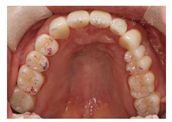

12、24、34、44牙缺失,12牙缺失牙间隙无,13牙与11牙建立邻接,24、34、44牙缺失牙间隙减少。咬合检查:上颌牙中线与面中线一致,下切牙中线右偏约1.5mm,11、13牙对刃,前牙部分开

,21、22、23、43牙与对侧牙无咬合接触,后牙有咬合,磨牙中性关系。余检查同术前(图8,图9,图10,图11)。